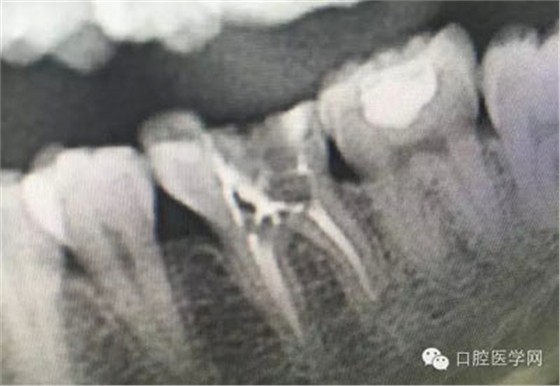

這是一例外院樹脂修復(fù)后十個(gè)月出現(xiàn)牙髓炎癥狀的患者。遇到這樣子的患者大家會(huì)怎么做,證明選擇,還有就是可做可不做治療的如何去平衡。